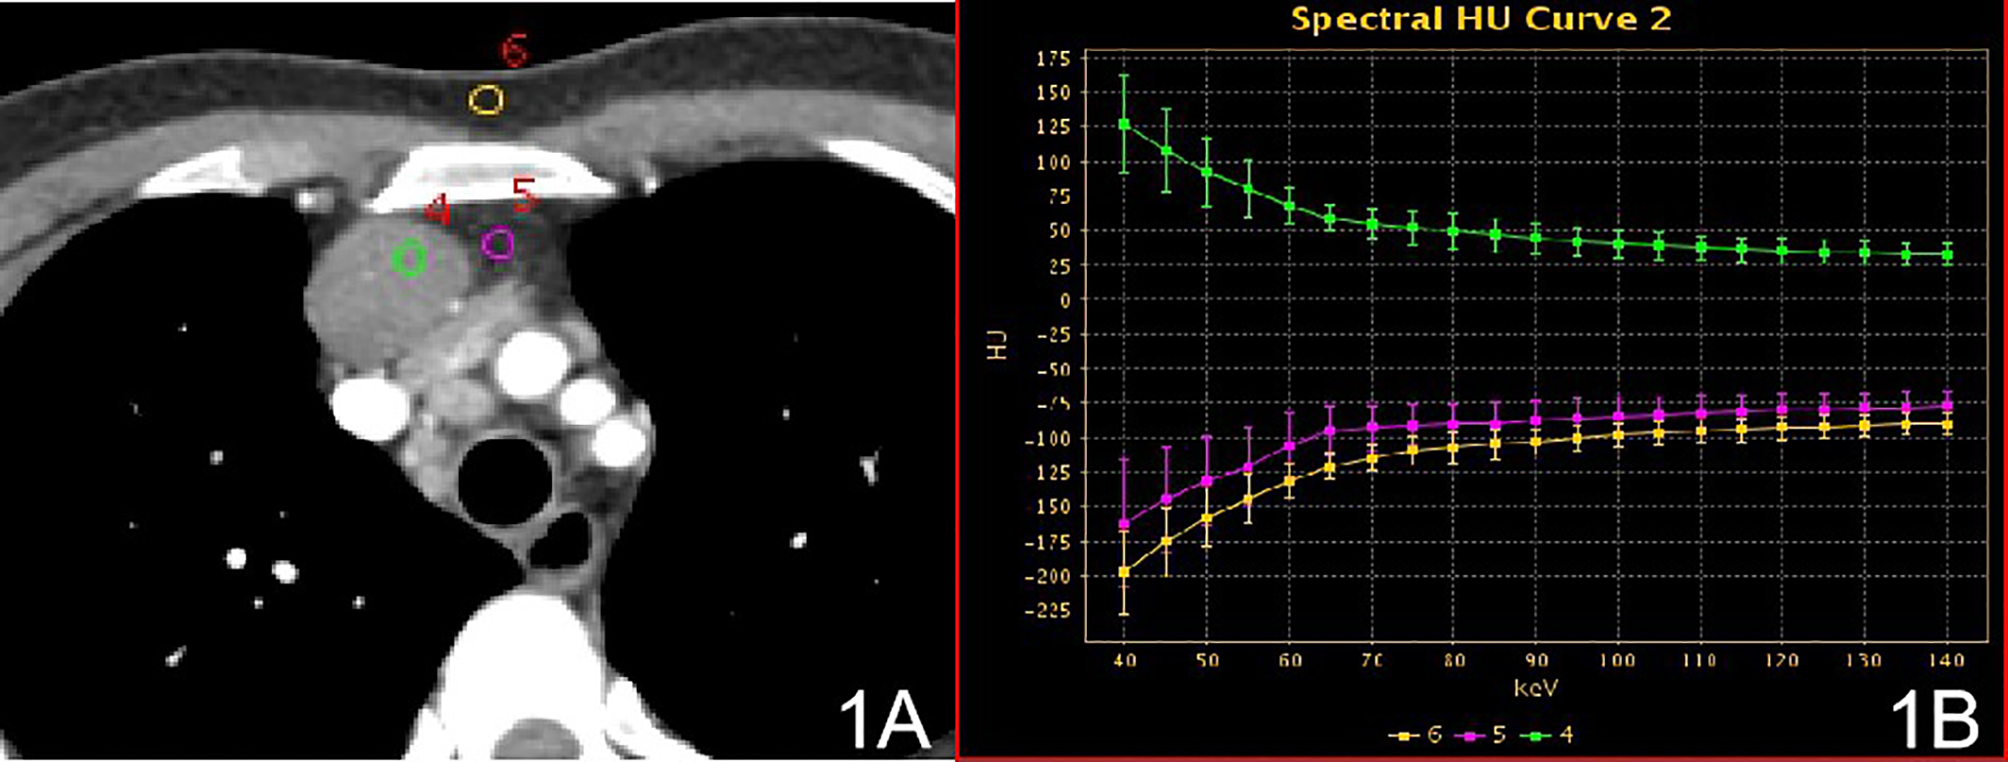

Figure 1

Stage I, (A) 70 keV single-energy CT value of the arterial phase is used to outline the ROI of the lesion; (B) spectrum of arterial lesions (green), spectrum of fat outside the lesion (purple) and spectrum of anterior chest wall fat (yellow).

In stage I, the difference in the slope of the energy spectrum curve of tumor parenchyma, tumor extracapsular fat, and anterior chest wall fat was statistically significant (P < 0.001, P < 0.001) (Table 2) (Figure 1). In stage II, the difference between the tumor parenchyma, the fat outside the tumor, and the slope of the spectrum curve of the anterior chest wall was statistically significant (P < 0.001, P < 0.001) (Table 3) (Figure 2). According to the slope of the energy spectrum curve of the outer fat layer of the lesion, combined with the energy spectrum curve graph, the accuracy of spectral CT for predicting the Masaoka-Koga stage I and II lesions was 79.4%.

The 54 patients evaluated in this study included 19 with stage I, 15 with stage II, 8 with stage III lesions, and 12 with stage IV lesions according to the Masaoka-Koga staging. The 54 patients were divided into three groups: non-invasive group (stage I), invasive surrounding fat group (stage II), and invasive surrounding structures (pleura, pericardium, lung, blood vessels) and distant metastasis group (stages III and IV). In the qualitative diagnosis, irregular or lobed edges lesions on conventional CT. It may indicate that the tumor capsule and extracapsular fat have been invaded (25). In this study, ROIs were delineated in stage I and stage II solid lesions, extracapsular fat, and anterior chest wall fat. The energy spectrum curves for the lesion, extracapsular fat, and anterior chest wall fat were obtained. In stage I lesions, the energy spectrum curve of the tumor parenchyma and the energy spectrum curve of the extracapsular fat have the opposite shape, and the energy spectrum curve of the extracapsular fat and the front chest wall fat have the same shape, indicating that the lesion did not extend outside the capsule. The slope of the spectrum curve for the anterior chest wall fat in stage II lesions showed statistically significant differences with those of the spectra for the lesion and the lesion’s extracapsular fat, indicating that the lesion had invaded the extracapsular fat. According to the spectrum curve, the lesion and the fat in the outer capsule of the lesion were homologous. In this study, ROIs were delineated in pathologically confirmed mediastinal lymph node with metastasis, intravascular tumor emboli, and solid lesions. The spectral curves for the metastatic lymph nodes, intravascular emboli, and lesions were consistent and the differences in the slopes were not statistically significant, indicating that the lesions were homologous to lymph nodes and intravascular emboli (26). Among these parameters, the energy spectrum curve objectively reflects whether the tumor parenchyma and extracapsular fat are homologous, and whether the enlarged lymph nodes and emboli are metastatic.